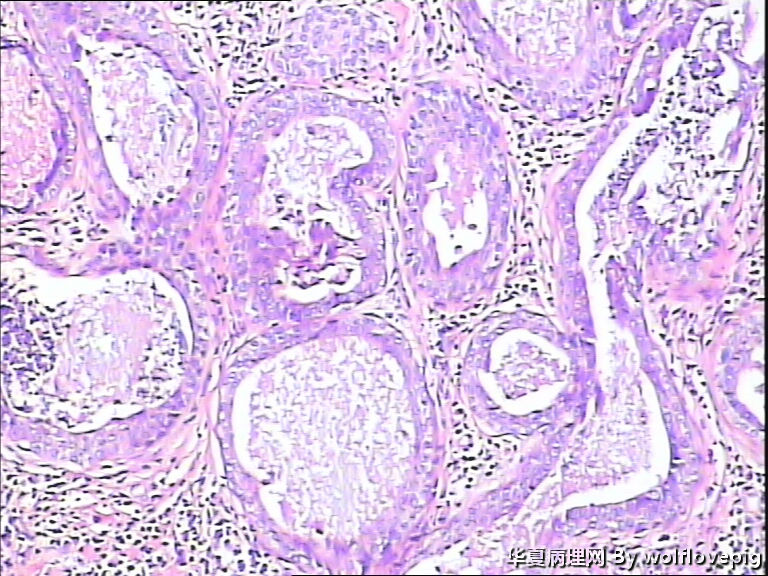

男,38y,腹部皮肤硬节20年。灰白不整形带皮组织一块:3.0*1.5*1.4cm,皮肤表面可见多个小结节样隆起。

图3